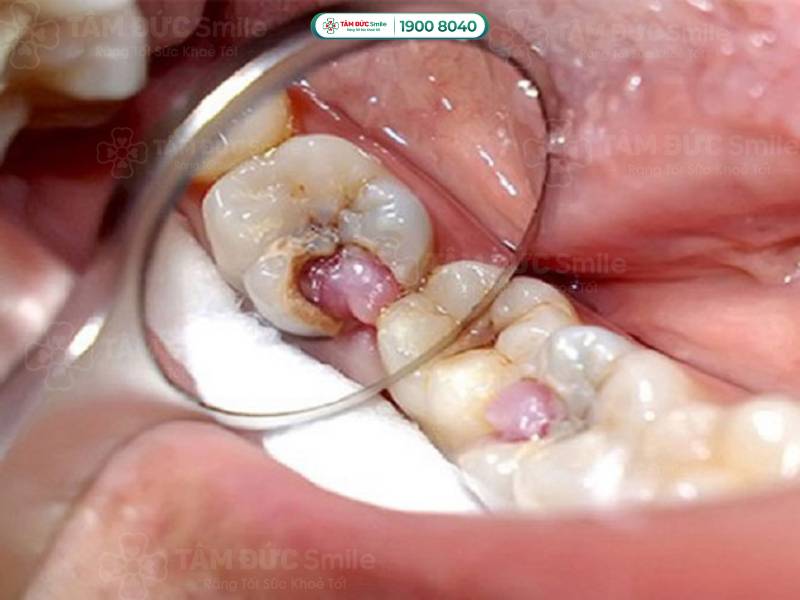

1.1.1. Răng sâu lồi thịt gây đau đớn, chảy máu răng

Răng sâu lồi thịt là răng đã viêm nhiễm nặng, lỗ sâu lớn nên vi khuẩn xâm nhập vào tủy răng. Phần niêm mạc bị sưng lên gây đau đớn, nhất là khi ăn nhai. Khi đánh răng hoặc chạm vào vùng răng bị sâu, Quý khách có thể thấy tia máu hoặc phần bọt đánh răng có máu đỏ.